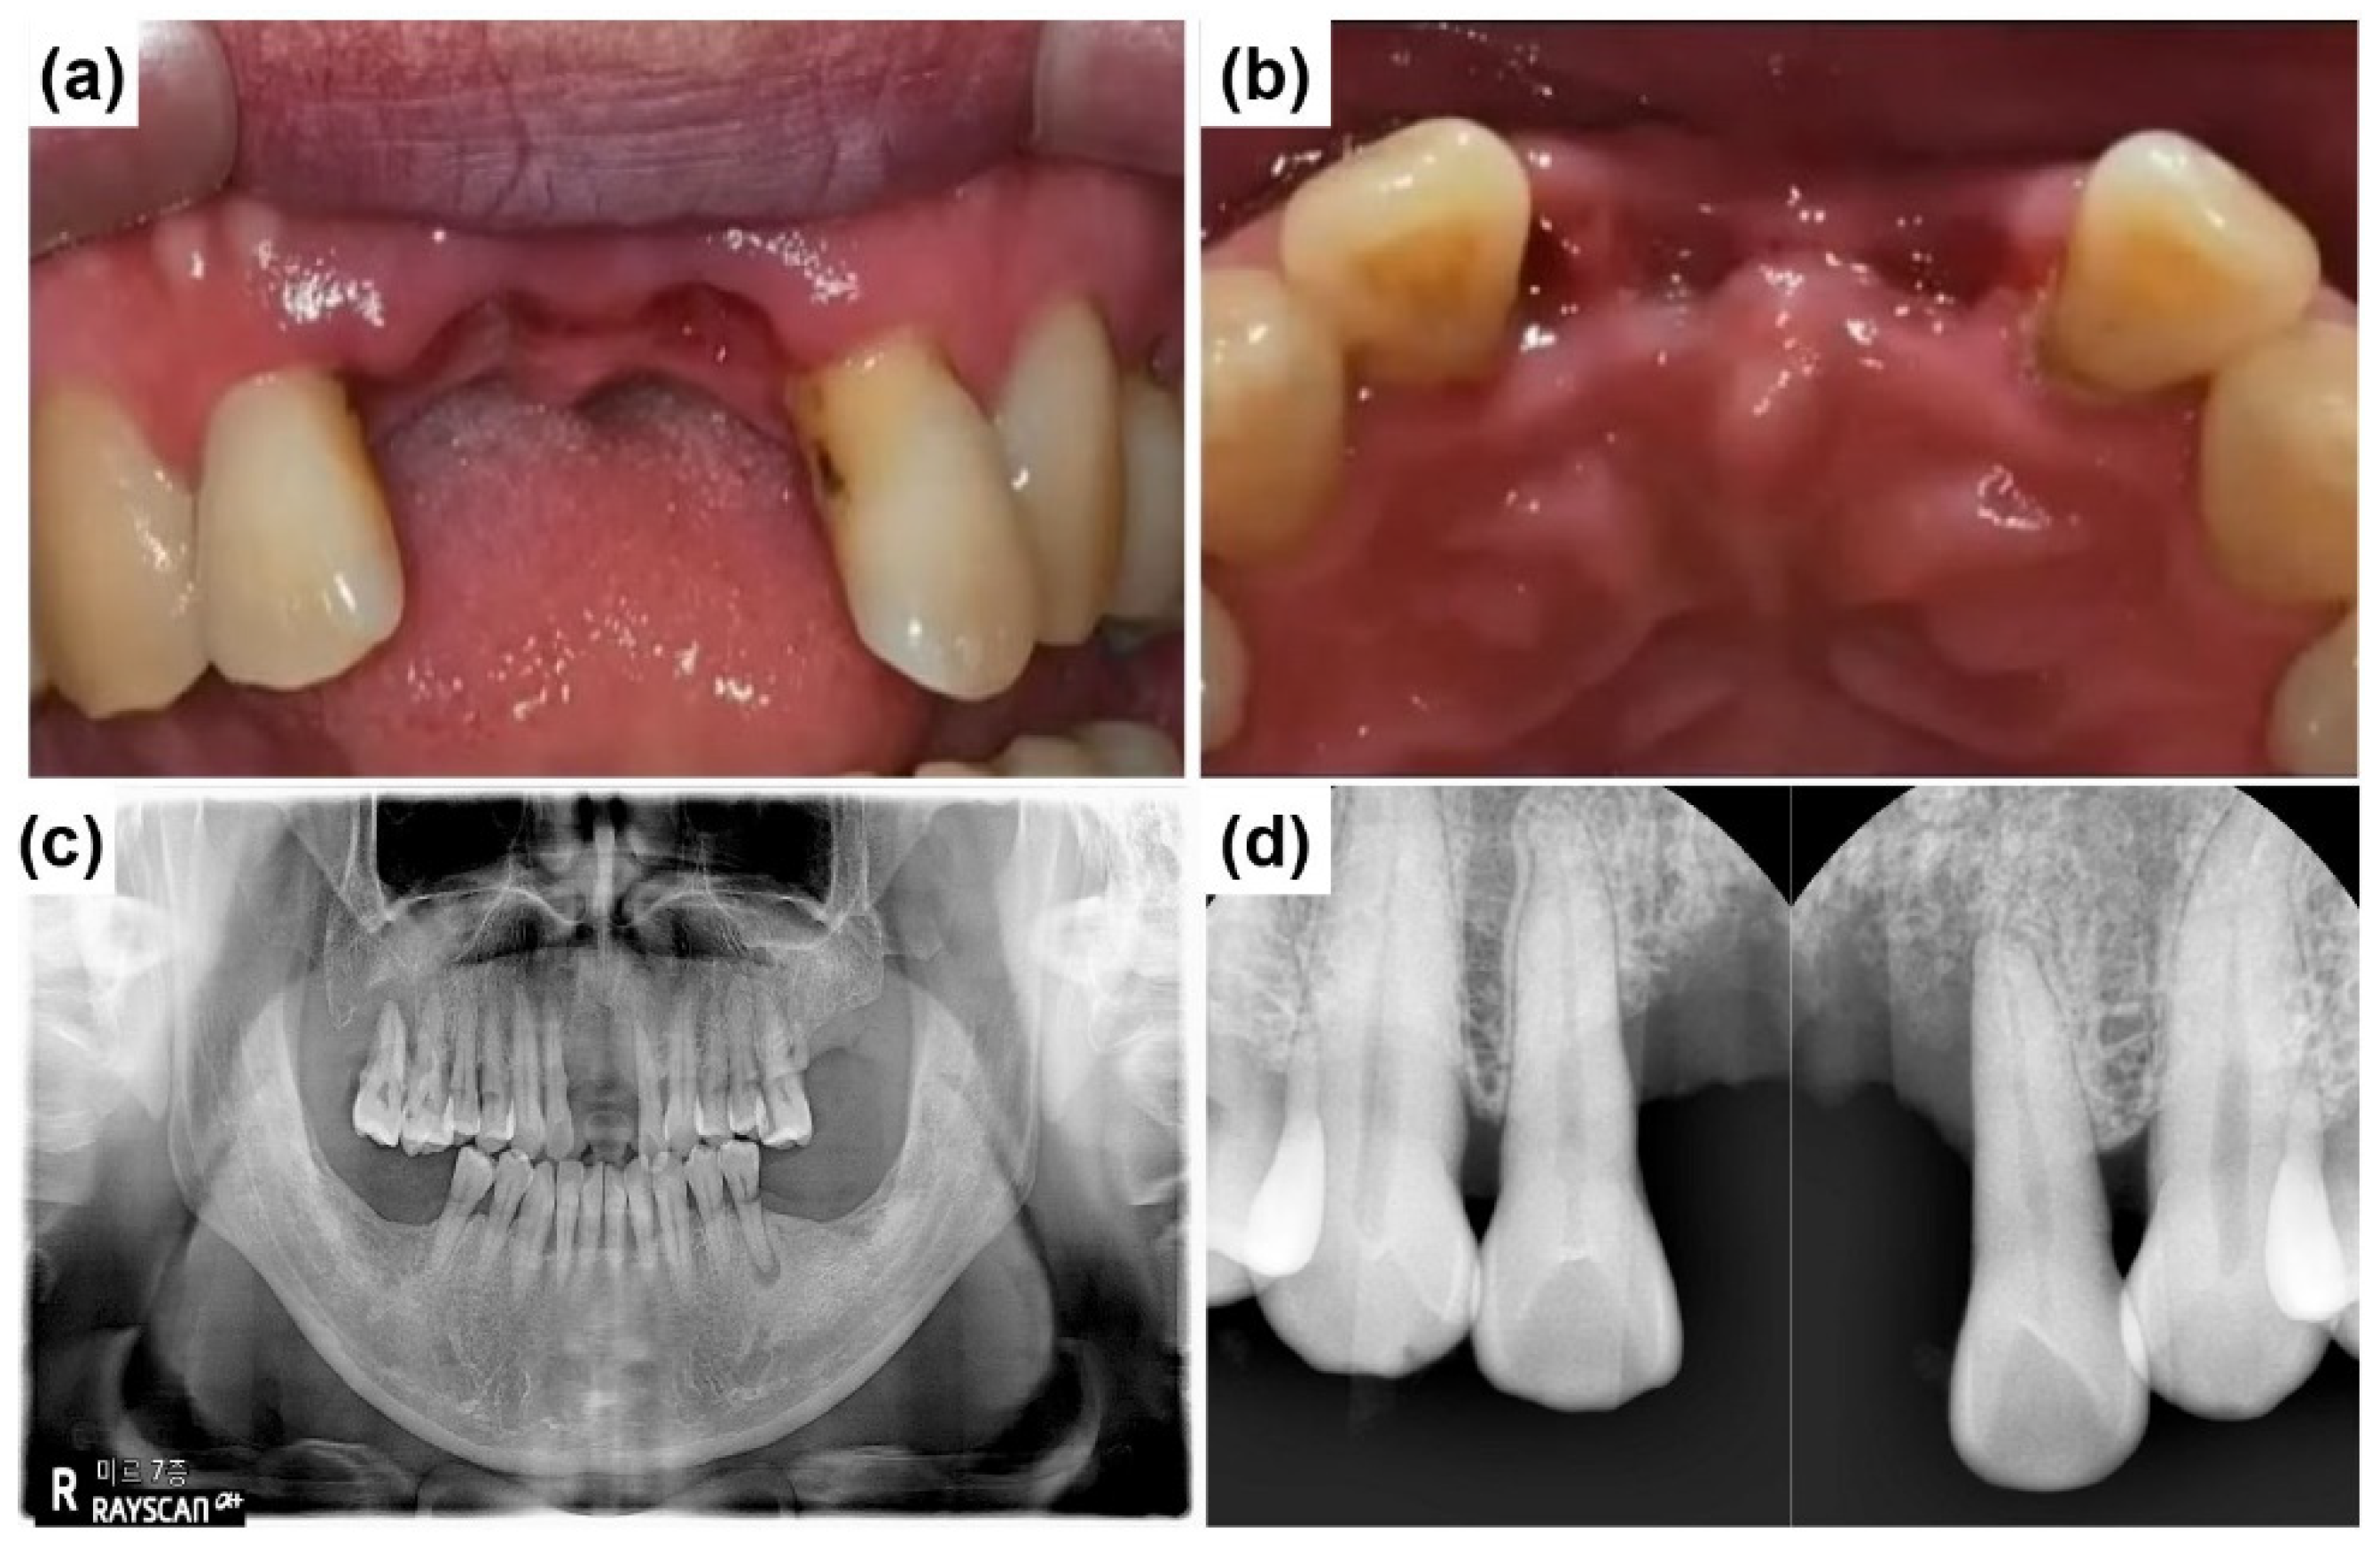

2.1. Case Report 1